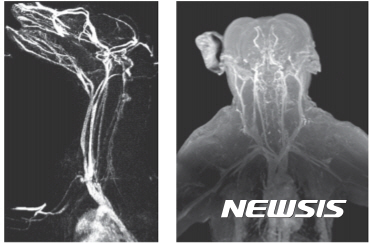

【대전=뉴시스】 산화철 나노입자 조영제를 이용해 개(사진 왼쪽)와 원숭이(오른쪽)를 촬영한 MRI 영상. (사진=IBS 제공)

원숭이와 개의 뇌 혈관에 조영해 촬영한 결과 뇌졸중 등 뇌 질환을 가진 동물을 정확하게 진단했다.

특히 조영효과가 기존 가돌리늄 조영제보다 뛰어나 뇌 혈류를 더 정확하게 진단할 수 있어 뇌졸중 진단과 치료에 도움이 될 것으로 기대된다.